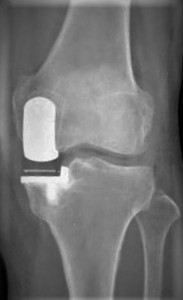

傷んだ関節表面を人工関節の形に合わせて削り、金属、セラミック、ポリエチレンでできた人工関節を骨の上に固定します。人工関節の耐久性は10年間弛みなく日常生活が送れる可能性が95%以上といわれ、長期的にも安定した方法です。

手術前

TKAの術後